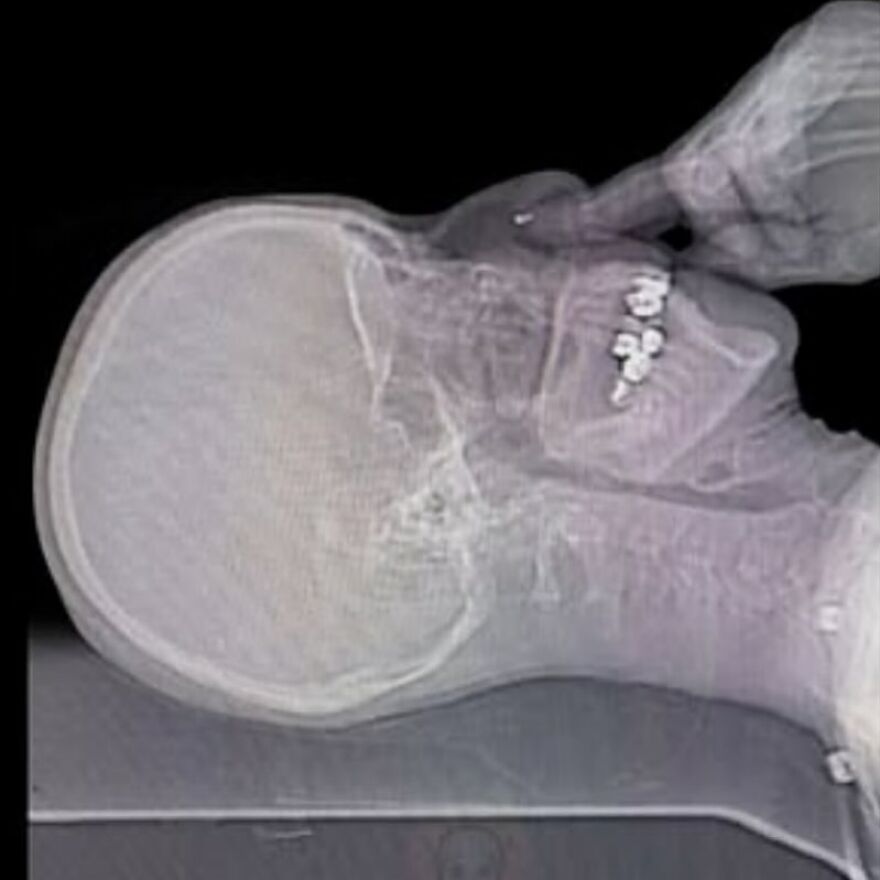

Skull of a person who had skeletal cancer